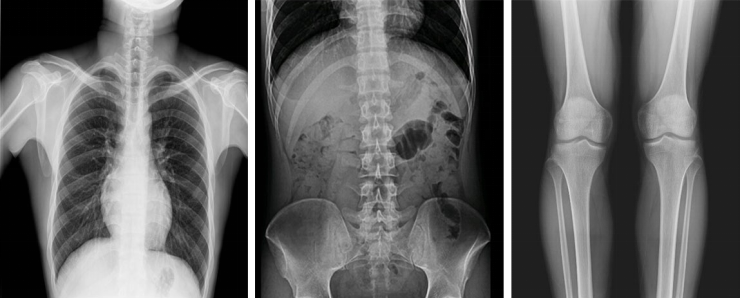

動(dòng)態(tài)DR影像采集幅面大,17×17英寸超大視野,可覆蓋成年人的全胸全腹,并且能在連續(xù)動(dòng)態(tài)中實(shí)時(shí)高清點(diǎn)片,還可以進(jìn)行視頻保存,在會(huì)診過(guò)程中可以回放影像檢查視頻,從而達(dá)到精準(zhǔn)診斷的目的。同時(shí)動(dòng)態(tài)DR還具有全身拼接功能,尤其適用于全脊柱和全下肢攝影,輔助脊柱畸形矯形治療、康復(fù)檢查,為臨床提供高精度圖像。